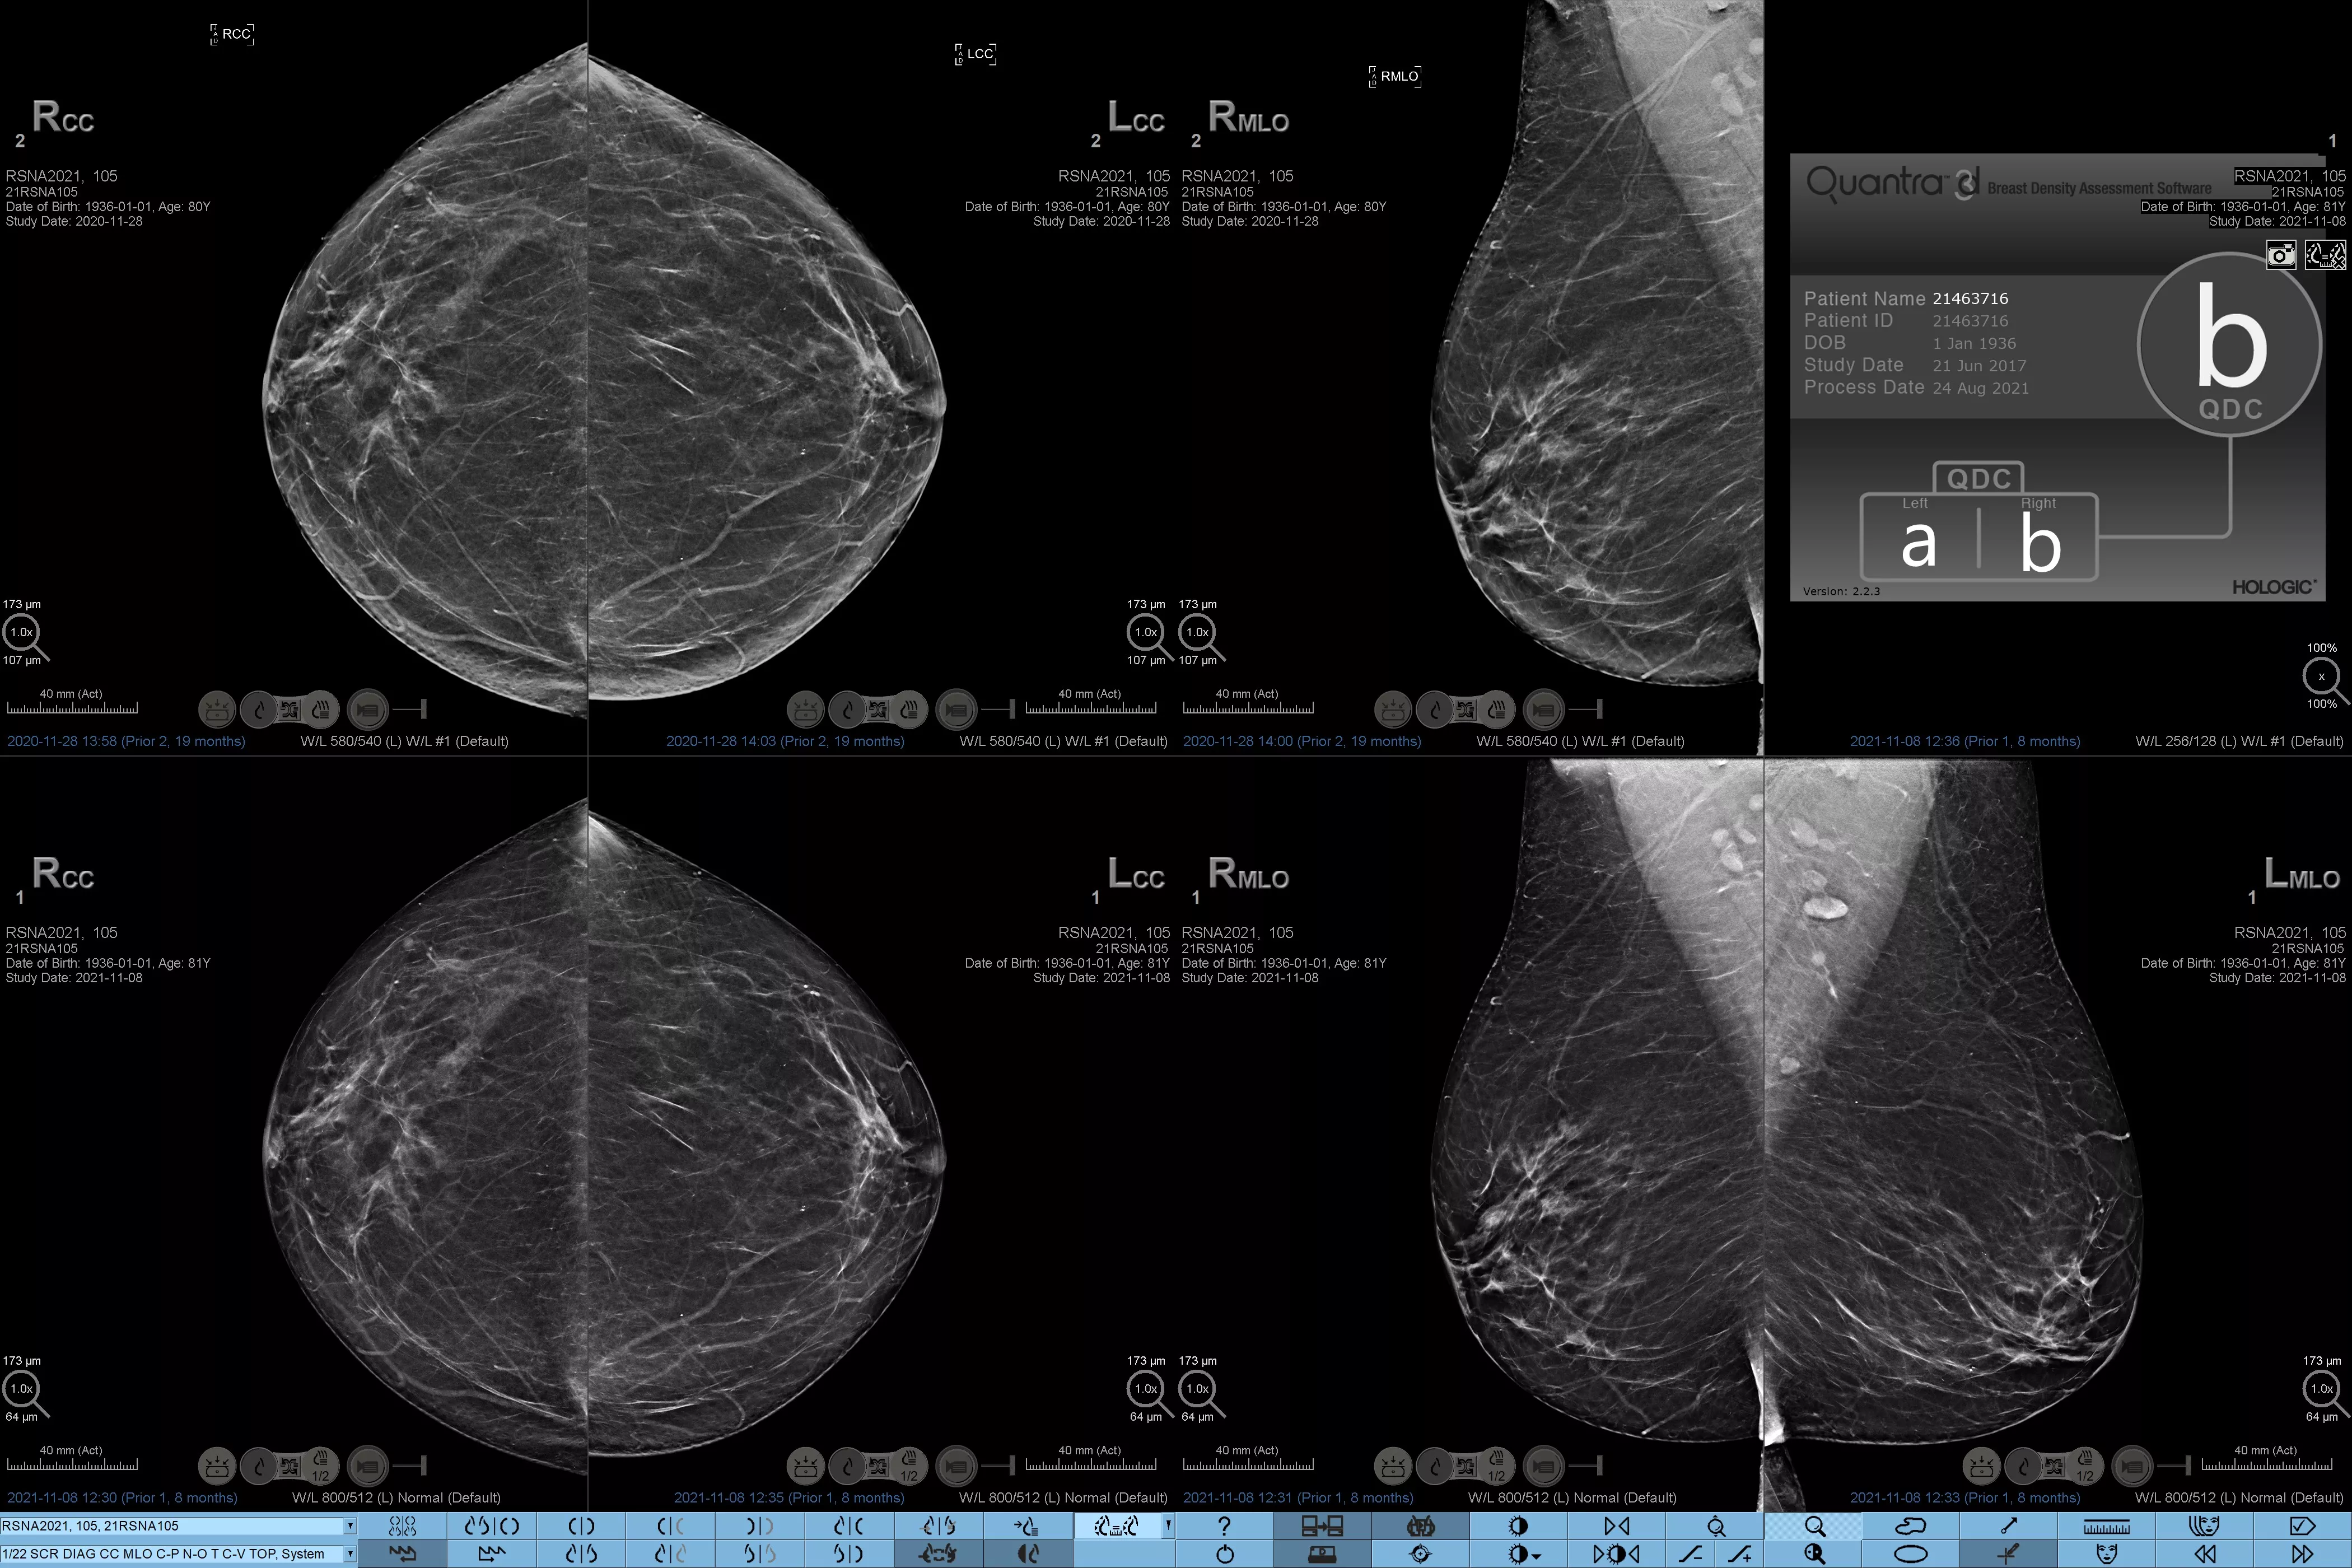

Sabemos que una densidad mamaria alta aumenta el riesgo de cáncer de mama en mujeres.1 Por tanto, es fundamental realizar un análisis preciso y sin sesgo. El software de la tecnología Quantra, basado en aprendizaje automático, analiza las imágenes 2D™ y de tomosíntesis para determinar la distribución y la textura del tejido parenquimatoso. Clasifica las mamas en cuatro categorías de composición mamaria de acuerdo con las directrices del Atlas BI-RADS (5.ª edición) del American College of Radiology (ACR).2

El algoritmo de aprendizaje automático objetivo asigna una categoría de densidad de mama de acuerdo con los patrones y la textura del tejido de la mama.

Estandarización

Aumente el estándar asistencial y normalice los informes en toda la consulta de radiología.

* Las clasificaciones se basan en las categorías BI-RADS del ACR, de acuerdo con las directrices revisadas publicadas en el Atlas BI-RADS (5.ª edición) del American College of Radiation (ACR). Estas directrices tienen en cuenta el patrón y la textura, y no solo el volumen, a la hora de determinar la densidad.